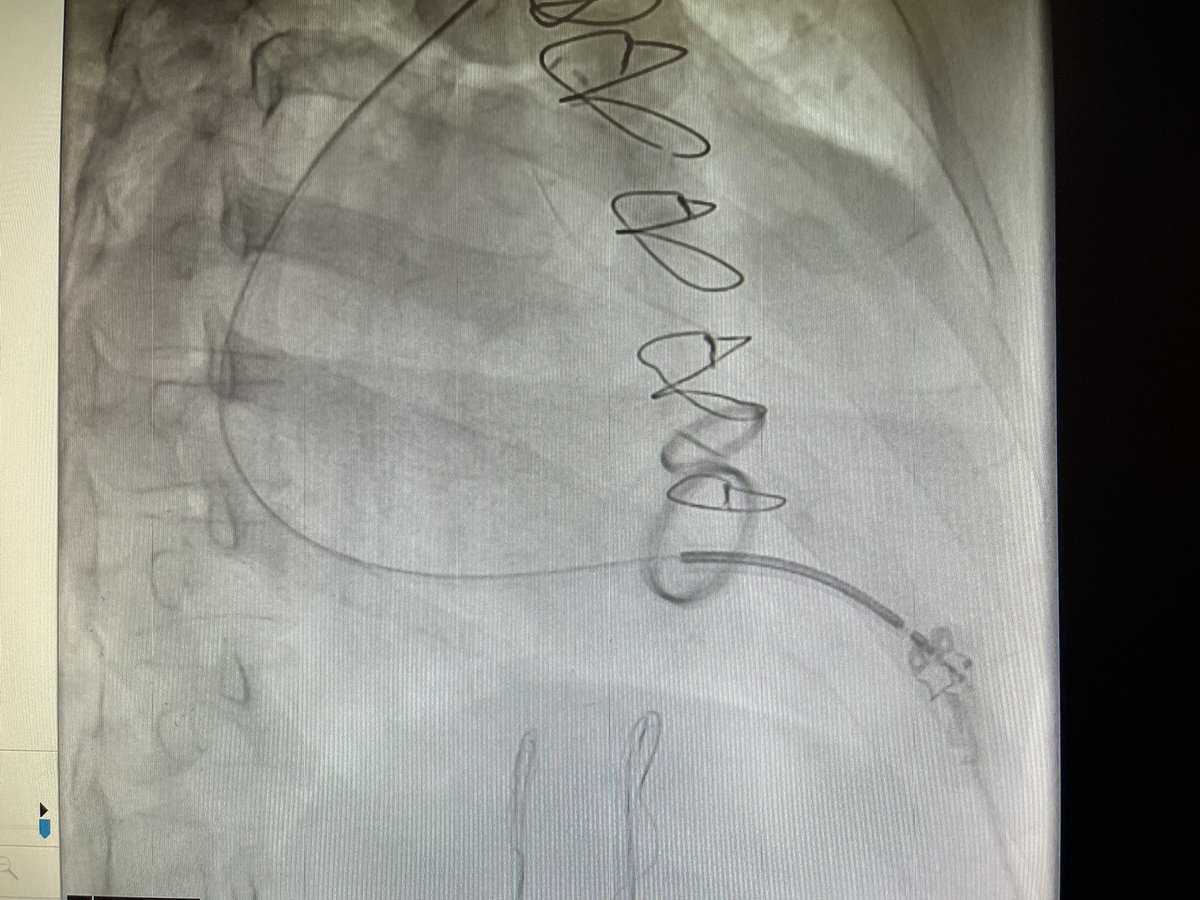

Is #PulseFieldAblation replacing RF Ablation?

Dr. Kristopher Heinzman & @pkothapalliMD explore its clinical promise, training risks & how EPs decide which patients fit PFA vs RFA.